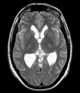

Colloid cyst of third ventricle

A colloid cyst is a non-cancerous tumor in the brain. It consists of a gelatinous material contained within a membrane of epithelial tissue. [Source: Wikipedia ]